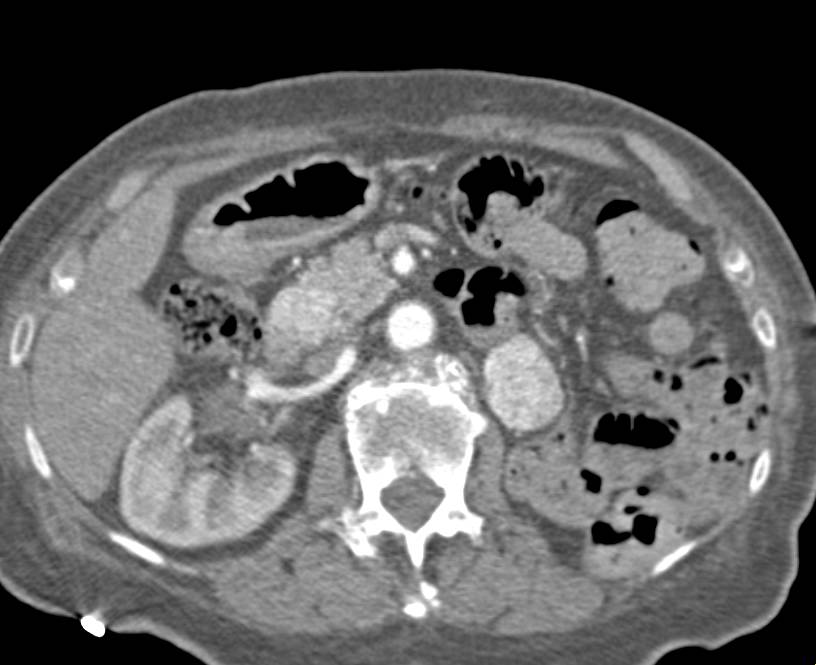

Left Renal Artery Aneurysm in 3D in Multiple Phases